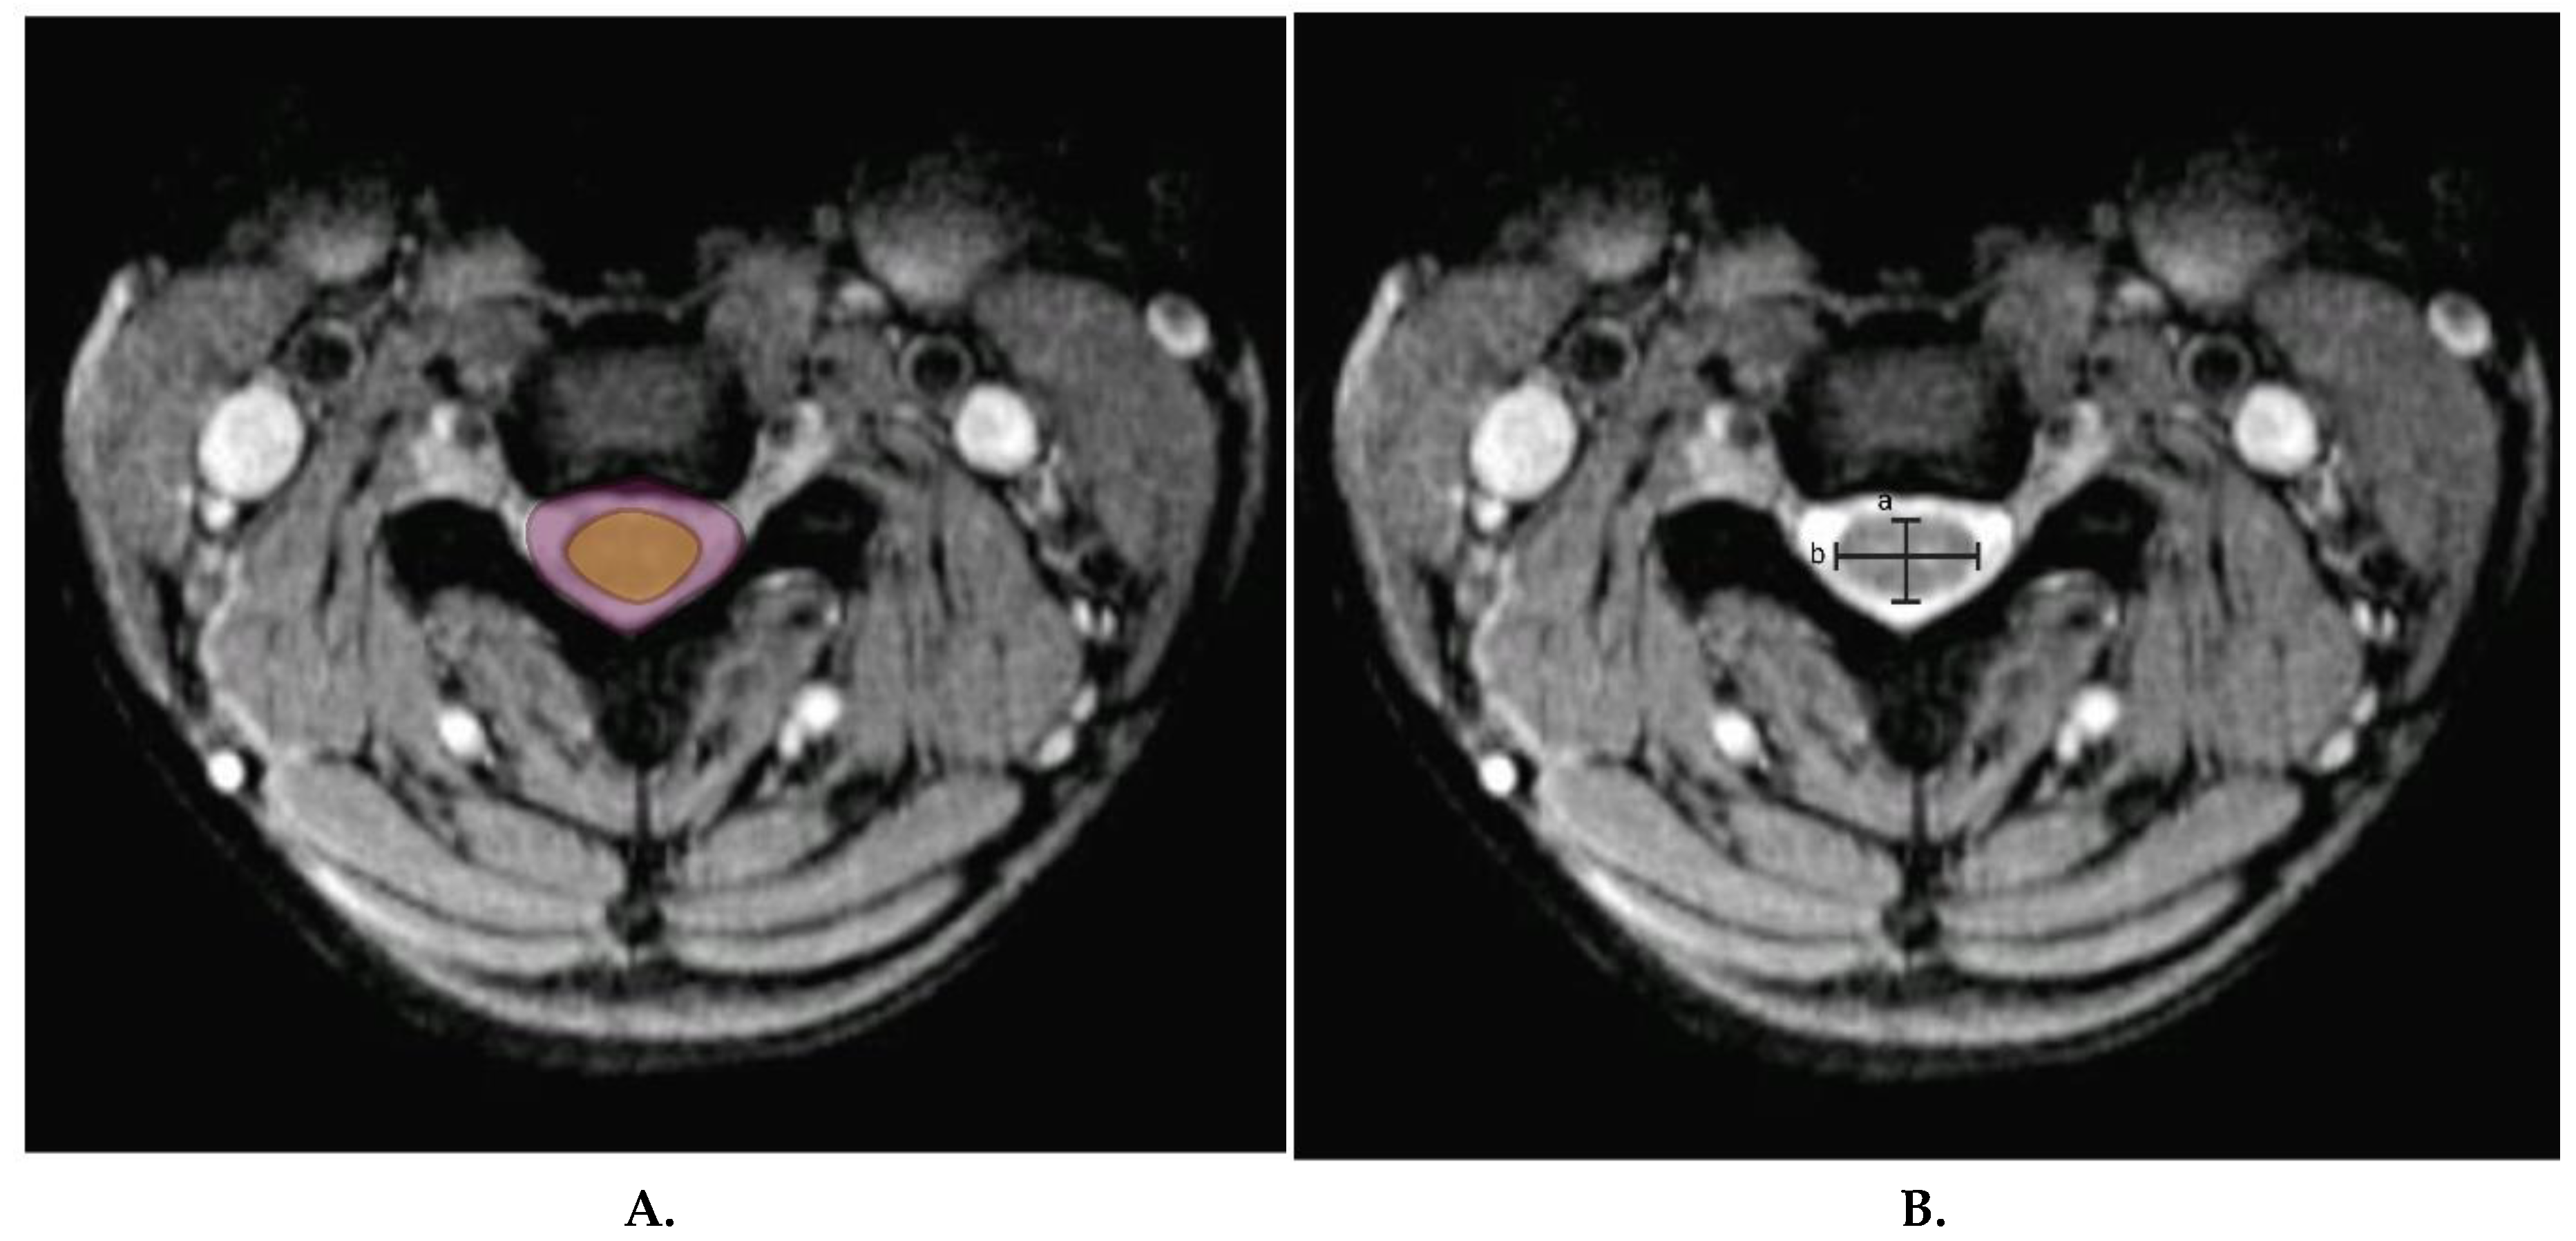

- Presciutti, S. M.; DeLuca, P.; Marchetto, P.; Wilsey, J. T.; Shaffrey, C.; Vaccaro, A. R. Mean subaxial space available for the cord index as a novel method of measuring cervical spine geometry to predict the chronic stinger syndrome in American football players. J Neurosurg Spine 2009, 11, 264–271. [Google Scholar] [CrossRef]

- Meyer, S. A.; Schulte, K. R.; Callaghan, J. J.; Albright, J. P.; Powell, J. W.; Crowley, E. T.; el-Khoury, G. Y. Cervical spinal stenosis and stingers in collegiate football players. Am J Sports Med 1994, 22, 158–166. [Google Scholar] [CrossRef]

- Kelly, J. D. t.; Aliquo, D.; Sitler, M. R.; Odgers, C.; Moyer, R. A. Association of burners with cervical canal and foraminal stenosis. Am J Sports Med 2000, 28, 214–217. [Google Scholar] [CrossRef]

- Greenberg, J.; Leung, D.; Kendall, J. Predicting chronic stinger syndrome using the mean subaxial space available for the cord index. Sports Health 2011, 3, 264–267. [Google Scholar] [CrossRef]

- Torg, J. S.; Naranja, R. J., Jr.; Pavlov, H.; Galinat, B. J.; Warren, R.; Stine, R. A. The relationship of developmental narrowing of the cervical spinal canal to reversible and irreversible injury of the cervical spinal cord in football players. J Bone Joint Surg Am 1996, 78, 1308–1314. [Google Scholar] [CrossRef]

- HERZOG, R. J.; WIENS, J. J.; DILLINGHAM, M. F.; SONTAG, M. J. Normal Cervical Spine Morphometry and Cervical Spinal Stenosis in Asymptomatic Professional Football Players: Plain Film Radiography, Multiplanar Computed Tomography, and Magnetic Resonance Imaging. Spine 1991, 16, S178–S186. [Google Scholar] [CrossRef]